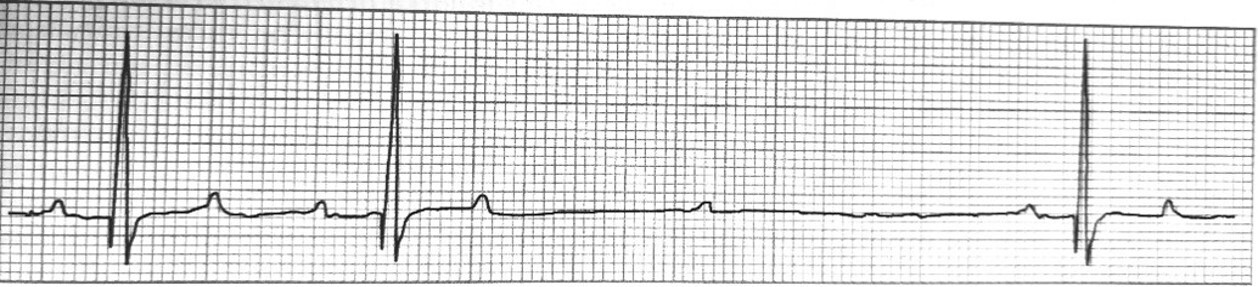

Vad visar EKGet och varför ser det ut så?

A

AV-block 1a graden

Ökad ledningstid genom AV-knutan –> förlängd P-R intervall.

Normal P-våg och QRS